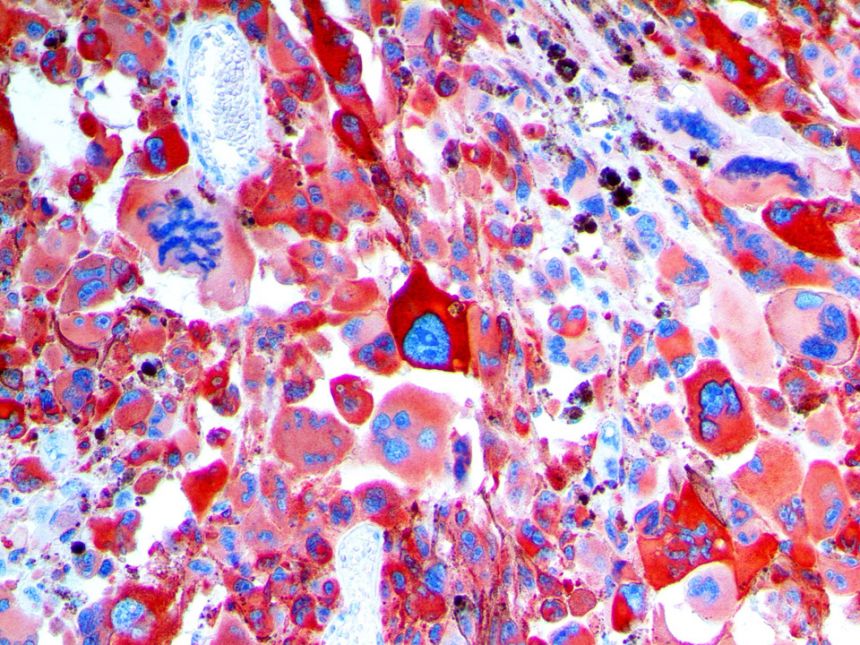

Clinical and laboratory manifestations of HLH include fever, enlarged liver and/or spleen, neurologic dysfunction, coagulopathy, liver dysfunction, cytopenias (i.e., low levels of erythrocytes, leukocytes, and/or platelets), hypertriglyceridemia, hyperferritinemia, hemophagocytosis, and eventually diminished NK cell activity as the immune system becomes progressively paralyzed. HLH can be familial (primary HLH) or secondary to another disease process (sHLH), such as rheumatic disease, in which it is referred to as macrophage activation syndrome (MAS, characterized by elevated ferritin).

This activation induces inflammatory monocytes to highly express IL-6, starting a localized and then systemic cascade effect that results in hyperproduction of IL-6, which accelerates the inflammatory process. Because IL-6 also increases vascular permeability, excessive levels cause blood vessels to become very leaky. This, along with clotting factors released from vascular endothelial cells, stimulates the coagulation cascade, resulting in microthrombosis (tiny clots), which leads to ischemia and tissue death of the kidney, intestines, heart, liver, brain and extremities.